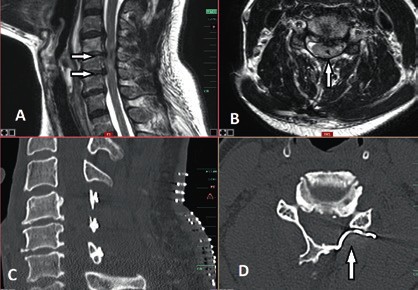

Die operative Therapie ist unabdingbar im Falle von Wirbelsäuleninstabilität und/oder Rückenmarkkompression mit progredienter inkompletter Querschnittsymptomatik. In diesen Fällen besteht ein breiter Konsens, dass die operative Versorgung bei älteren Patienten eine dringende Indikation und in den Fällen sukzessiver neurologischer Verschlechterung eine Notfallindikation darstellt. Dagegen ist es bei der Indikationsstellung zur operativen Therapie bei stabilen, jedoch degenerativen Wirbelsäulen mit posttraumatischen Querschnittverletzungen schwieriger, einen Konsens zu finden 14 15. In diesen Fällen ist die Evaluation der potenziellen Vorteile einer Dekompression der neuralen Strukturen entscheidend für die Indikationsstellung einer operativen Therapie. Die Dynamik des posttraumatischen neurologischen Status spielt hier die entscheidende Rolle in der Evaluation. So werden Patienten mit komprimierender Spinalkanalstenose und zunehmender neurologischer posttraumatischer Verschlechterung von einer Dekompression des Spinalkanals mit großer Wahrscheinlichkeit profitieren (Abb. 6). Auch wenn die neurologische Erholung des Rückenmarks ungewiss bleibt, entfernt eine ausreichende Dekompression die schädigungsbegünstigende Ursache und beendet in den meisten Fällen die Verschlechterungsdynamik. Auch in den Fällen, in denen eine komplette Querschnittläsion besteht, kann die Dekompression perfusionsbedingte Sekundärschäden verhindern.